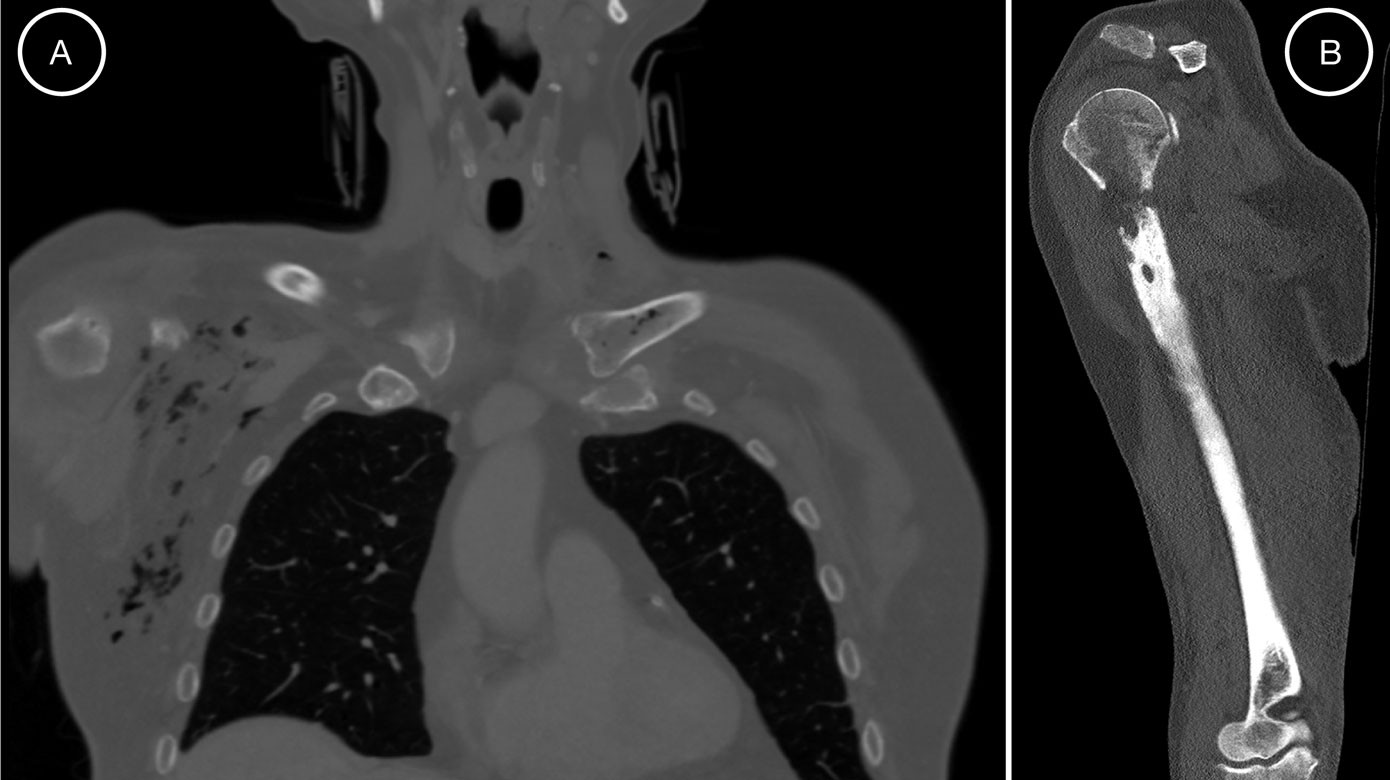

Figure 1 from Osteomyelitis Caused by Ralstonia mannitolilytica, a Rare Osteomyelitis Zosyn It is an inflammatory process involving the bone and its structures caused by pyogenic. Osteomyelitis is a serious infection of the bone that can be either acute or chronic. Antibiotics with good penetration profiles in bone and joints represent potential options for the treatment of osteomyelitis and. It may be acute or chronic. Complex bone and joint infections are typically. Osteomyelitis Zosyn.